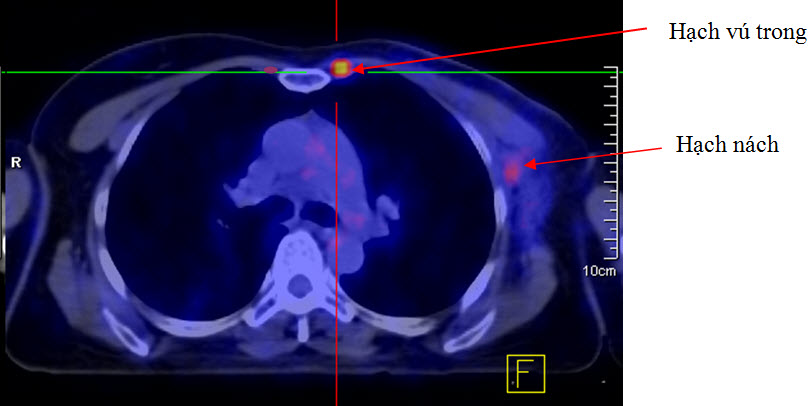

Trong xạ trị ung thư vú thì hạch vú trong được cân nhắc chỉ định xạ trị tùy theo mức độ bị di căn. Rất khó có thể đánh giá di căn hạch vú trong trên hình ảnh CT. Trong những trường hợp này mô phỏng trên PET/CT sẽ có nhiều ưu việt hơn. PET/CT cho phép đánh giá chính xác sự di căn hạch vú trong với độ nhạy rất cao.

Hình 7. Bệnh nhân Nguyễn Th. M. T., nữ, 51 tuổi, chẩn đoán: Ung thư vú trái đã phẫu thuật. Bệnh nhân được chụp PET/CT mô phỏng lập kế hoạch xạ trị hậu phẫu. Trên hình PET/CT mô phỏng thấy rõ hạch nách trái và hạch vú trong. (Nguồn: Mai Trọng Khoa – Trung tâm Y học hạt nhân và ung bướu – BV Bạch Mai)